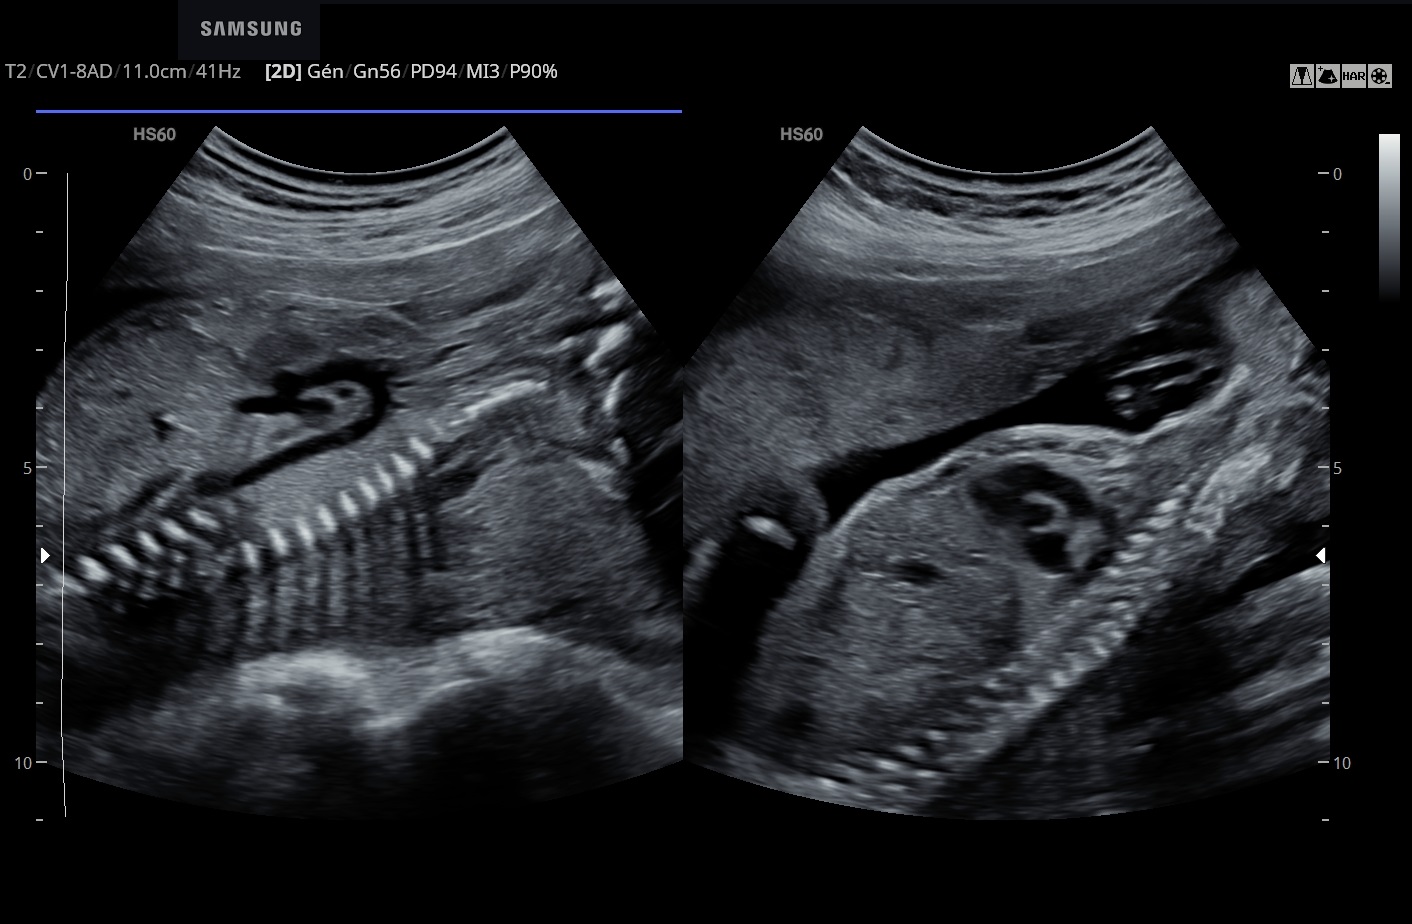

Le BiometryAssist™ est une technologie de biométries semi-automatisées qui permet à l'utilisateur de gagner en efficacité et en productivité.

Les sondes de technologie S-Vue™ disposent d'une sensibilité accrue et d'une bande passante plus large que les sondes conventionnelles. Elles garantissent une résolution d’image optimale, même chez les patientes techniquement difficiles. De plus la petite taille et la légèreté de ces sondes améliorent les conditions d'examen au quotidien.